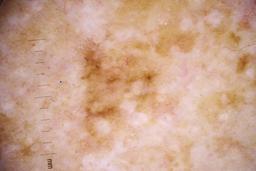

- Name: Challenge 2020: Training

- Number of images: 33,126

- Number of specified lesions: 32,701

- Number of specified patients: 2,056